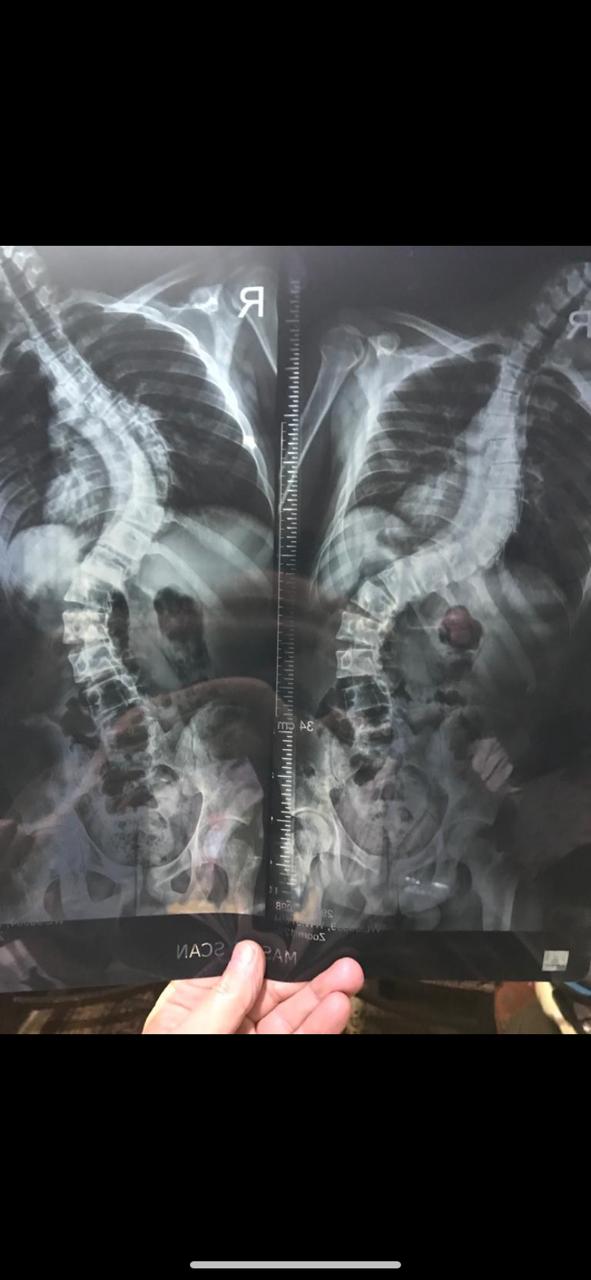

وأوضحت الهيئة أن المريض، يبلغ من العمر 20 عامًا، وكان يعاني من عدم القدرة على الحركة، وأن الفحوصات الطبية أظهرت إصابته بإعوجاج حاد وتشوهات في العمود الفقري بدرجة كبيرة مصاحب بأعراض مرضية، مشيرة إلى أنه تم إجراء العملية للمريض بنجاح واستقرار حالته الصحية.